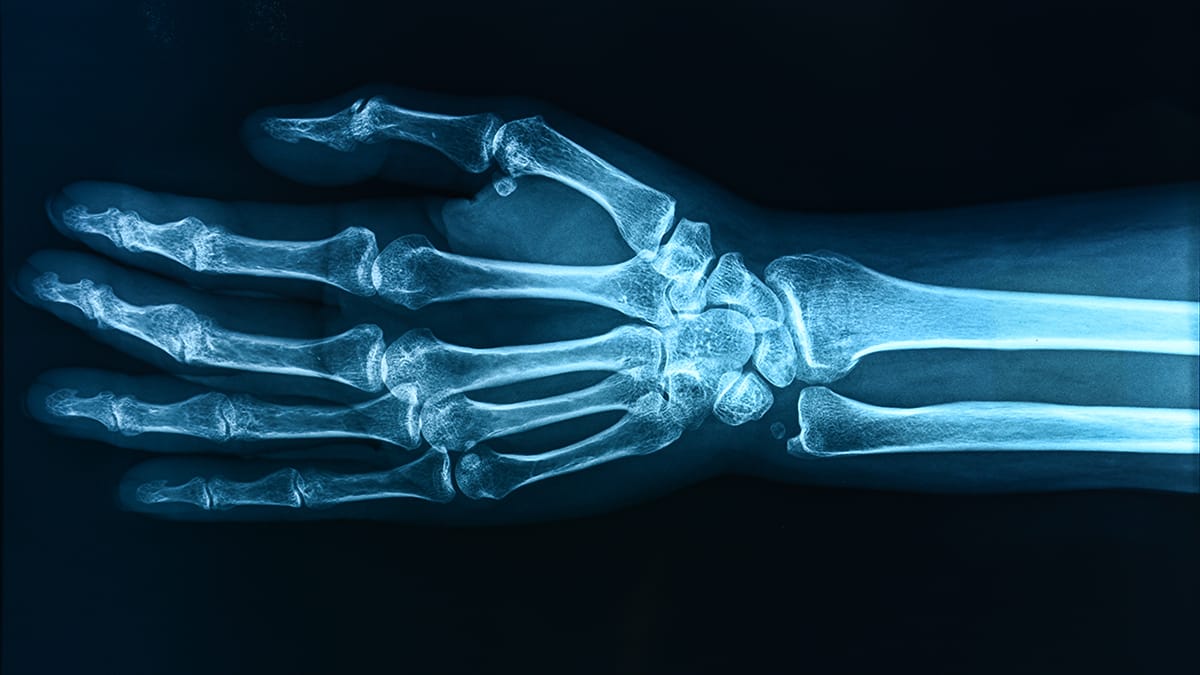

A pesquisa analisou dados de saúde de 218 crianças, correlacionando os níveis de PFAS em seus organismos com a densidade óssea. Os resultados indicaram uma associação entre o ácido perfluorooctanoico (PFOA) e a redução da densidade óssea nos antebraços de meninas de 12 anos. Além disso, a pesquisa sugere que a exposição a PFAS pode ter efeitos duradouros na saúde óssea, especialmente durante períodos críticos de desenvolvimento.

Os pesquisadores utilizaram um estudo observacional, onde não houve intervenção direta. Eles mediram os níveis de PFAS, incluindo PFOS, PFHxS e PFNA, em amostras de sangue e compararam esses dados com medições de densidade óssea em diferentes idades. A análise revelou que a idade é um fator crucial na relação entre a exposição a PFAS e a saúde óssea.

Os resultados indicam que a exposição a PFAS pode aumentar em até 30% o risco de fraturas ósseas em crianças. A pesquisa também sugere que a presença de PFAS pode interferir na absorção de vitamina D, um nutriente essencial para a formação óssea. A epidemiologista Jessie Buckley, da Universidade da Carolina do Norte, enfatiza a importância de reduzir a exposição a esses químicos durante as fases de desenvolvimento infantil para promover uma saúde óssea mais robusta ao longo da vida says.